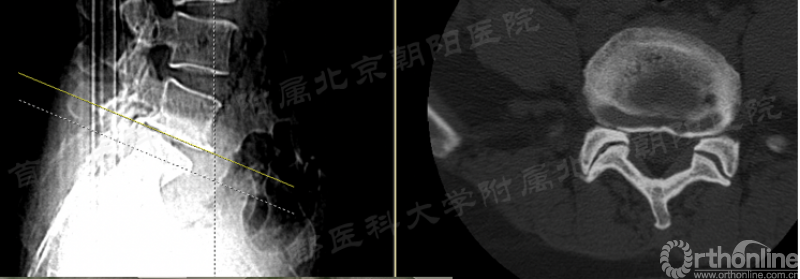

b. 第91例,第一次神经损伤,也希望是最后一例。

第91例,L2/3节段I-2-a区LDH。在置管后患者诉左下肢屈髋较对侧无力,无下肢放射痛及麻木,术中透视如图(红框)所示。镜下摘除髓核后将工作通道朝向背侧观察神经,患者诉颈部疼痛(脊髓高压症),镜下发现硬膜缺损(红箭头),但神经结构完整。立即结束手术。术后髂腰肌肌力IV级,大腿前方感觉减退,术后复查CT显示L3上关节成型后游离骨块导致出口神经受压。

4、在行关节突成型时应警惕尖部骨块游离挤压出口神经的可能性。